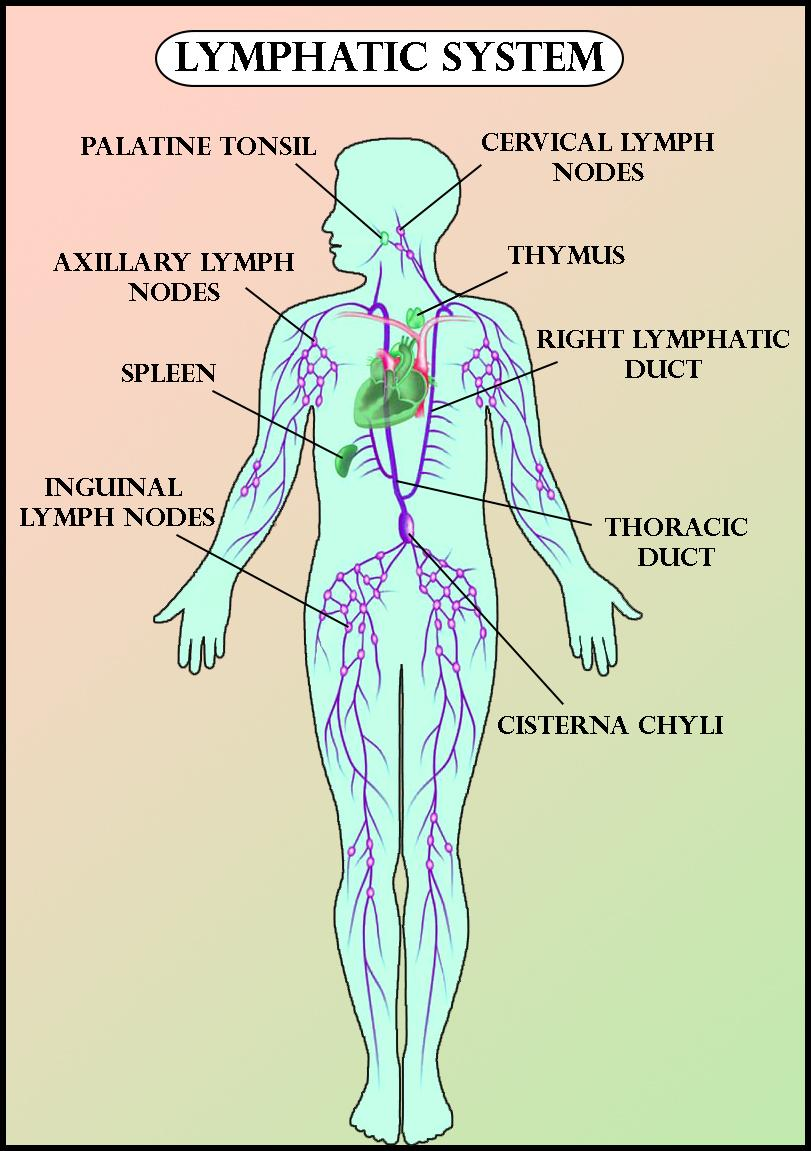

Lymphatic System

biology-diagrams.blogspot.com

biology-diagrams.blogspot.com